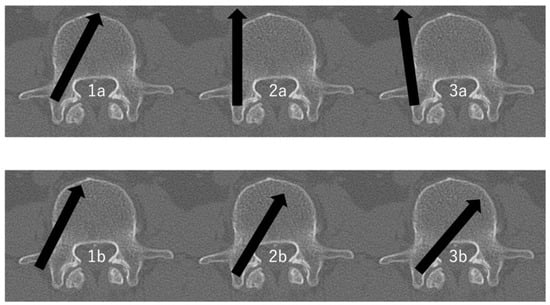

Figure 1.

The evaluation of PPS positioning within the pedicle [,]. 1a: >Half of pedicle screw diameter within the pedicle and >half of pedicle screw diameter within the vertebral body. 1b: >Half of pedicle screw diameter lateral outside the pedicle and >half of pedicle screw diameter within the vertebral body. 2a: >Half of pedicle screw diameter within the pedicle and >half of pedicle screw diameter lateral outside the vertebral body. 2b: >Half of pedicle screw diameter within the pedicle and tip of pedicle screw crossing the middle line of the vertebral body. 3a: >Half of pedicle screw diameter lateral outside the pedicle and >half of pedicle screw diameter lateral outside the vertebral body. 3b: >Half of pedicle screw diameter medial outside the pedicle and tip of pedicle screw crossing the middle line of the vertebral body. Arrows indicate the direction of screw insertion.